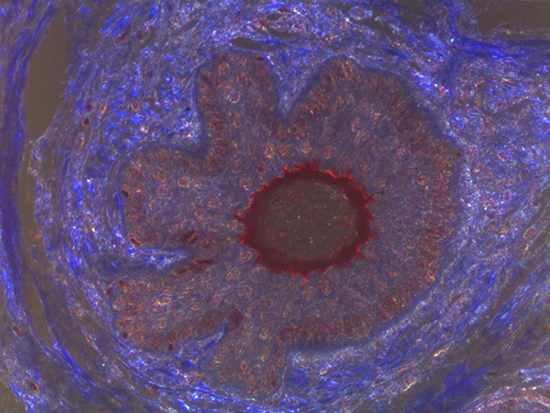

Masson's trichrome stain is incredibly effective in differentiating cells and their components from the surrounding connective tissues. One of the most common stain types, which has been used on the dermal tissue sample seen in the images within this article, yields a number of colors where cell nuclei appear dark red, collagen and other tissues appear green or blue, and cell cylasm appear red/purple (Jones, 2010). These stains have been imaged under brightfield and darkfield illumination, and then again with specific filters to selectively focus on the cellular constituents of the epidermis. The primary application for the epidermal trichrome stains is differentiating healthy collagen and muscles from connective tissues onset with tumorigenesis. Typically the tumors proliferate from muscle cells and fibroblasts deep in the dermal tissue (Blitterswijk, 2010).

Figure 2: Darkfield Imaging of Dermal Tissue

When comparing Figures 1 and 2, the visual differences are significant. A brightfield image is formed with the illumination source below the sample, and then transmitted light propagates through the sample to the sensor forming a bright, white background with sharp color. A darkfield image is formed by directing light at an oblique angle through the sample, forming a hollow cone of light which is collected by the objective. Darkfield illumination typically yields a dark background with sharp color, but in the case of Figure 2, the collagen and muscle fibers interfered with the light path and caused a blur of light and color. The dark background is hardly evident and only two distinct colors are visible. When analyzing histological stains, brightfield illumination is the preferred technique for lighting a sample.